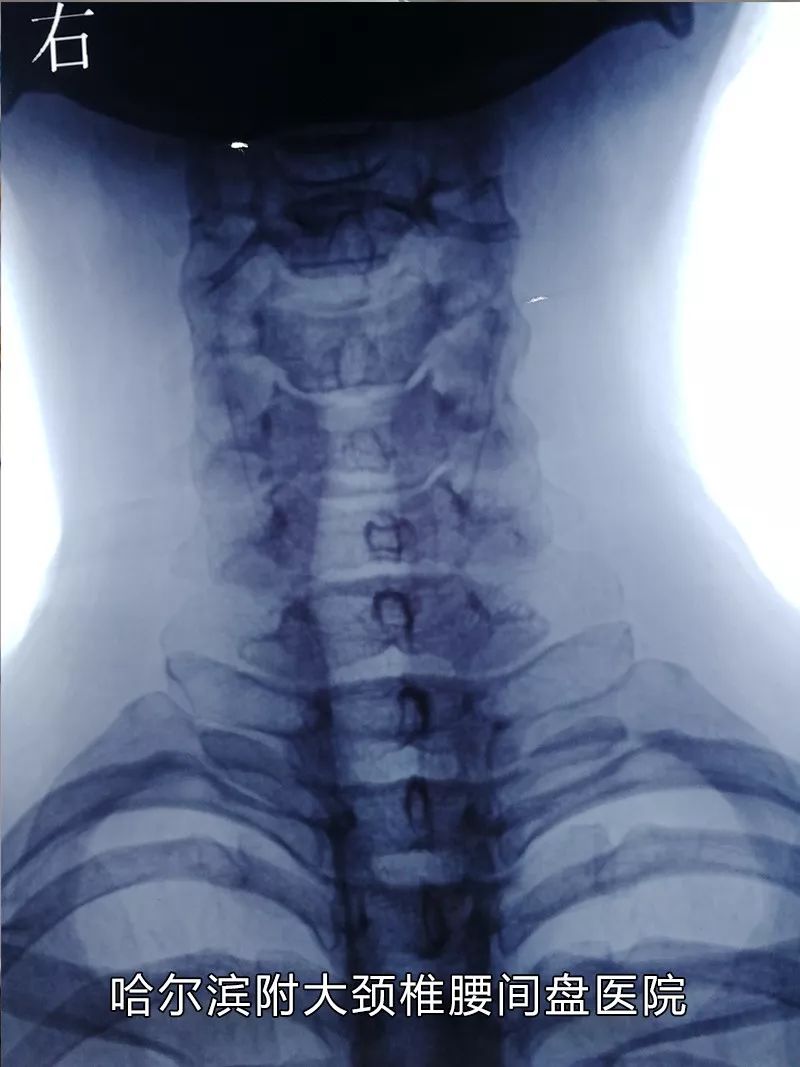

哈尔滨附大颈椎腰间盘医院业务院长、会诊中心主任。黑龙江中西医骨科学术委员会委员,发表学术论文十余篇、获得省市科研成果六项,出版医学专著一部、黑龙江省著名骨科专家。

擅长无创治疗疑难颈椎病、腰间盘突出、椎管狭窄等疾病。